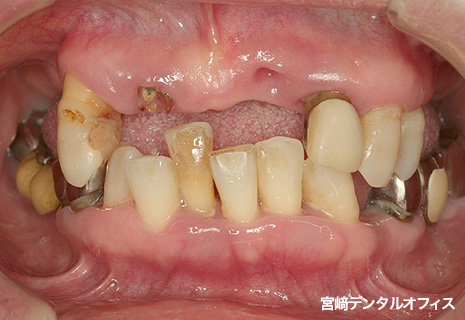

全顎的治療

術前

術後

インプラント治療